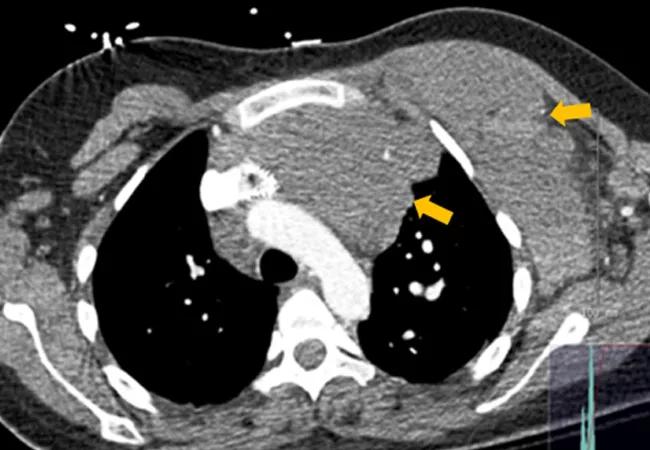

Chest computed tomography (CT) showed a huge venous malformation in the left anterior mediastinum lying immediately behind the sternum, extending across the midline anterior to the thoracic aorta and across the thoracic outlet into the left axilla and chest wall; the mass abutted the right ventricular outflow tract and the main pulmonary artery.

Figure 1. CT Chest